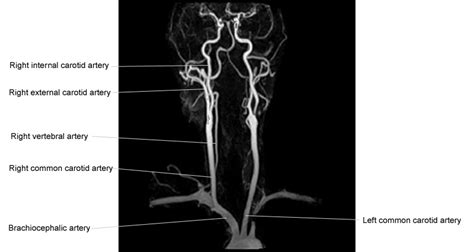

The content of the neck is grouped into 4 neck spaces, called the compartments. The cervical plexus is the main structure innervating or passing through the neck. Interactive diagrams show sinus cavity locations and help visualize sinusitis, the most common type of sinus. The neck is the start of the spinal column and spinal cord. There are four pairs of sinuses (named for the skull bones in which they're located). Like the head, the neck also houses several vital organs and structures such as the larynx, thyroid and parathyroid glands, trachea, and esophagus. The nerves of the head and neck include the most vital and important organs of the nervous system — the brain and spinal cord — as well as the organs of the special senses. Superficial dissections of the head and neck as seen in the gallery, show the many different muscles that are required for movement plus. Human anatomy diagrams show internal organs, cells, systems, conditions, symptoms and sickness information and/or tips for healthy living. Tackle it to learn more about the bones, vessels, muscles and organs of the head and neck! This diagram depicts head and neck anatomy.human anatomy diagrams show internal organs, cells, systems, conditions, symptoms and sickness information and/or tips for healthy living. Learn vocabulary, terms, and more with flashcards, games, and other study tools. This diagram depicts arteries of the neck and head.human anatomy diagrams show internal organs, cells, systems, conditions, symptoms and sickness information and/or tips for healthy living.

Anatomy of the head & neck. See anatomy of the head and neck stock video clips. As the head and neck anatomy is a hot topic among anatomy students, we have specially designed this head and neck anatomy quiz. Anatomy of the dog illustrated atlas this modules of vet anatomy provides a basic foundation in animal anatomy for students of veterinary. Internal and external pterygoid muscles contract on both sides, jaw moves forward. In addition, in this region we also find the major cranial and spinal nerves that connect the central nervous system to the organs, skin, and muscles of the head and neck. The neck muscles, including the sternocleidomastoid and the trapezius, are responsible for the gross motor movement in the muscular system of the head and neck. Neck muscles are bodies of tissue that produce motion in the neck when stimulated. This diagram depicts arteries of the neck and head.human anatomy diagrams show internal organs, cells, systems, conditions, symptoms and sickness information and/or tips for healthy living. The head and neck is covered in skin and its appendages, termed the integumentary system.these include hair, sweat glands, sebaceous glands, and sensory nerves.the skin is made up of three microscopic layers: There are four pairs of sinuses (named for the skull bones in which they're located). They move the head in every direction, pulling the skull and jaw towards the shoulders, spine, and scapula. 2 draw labelled diagram to show: